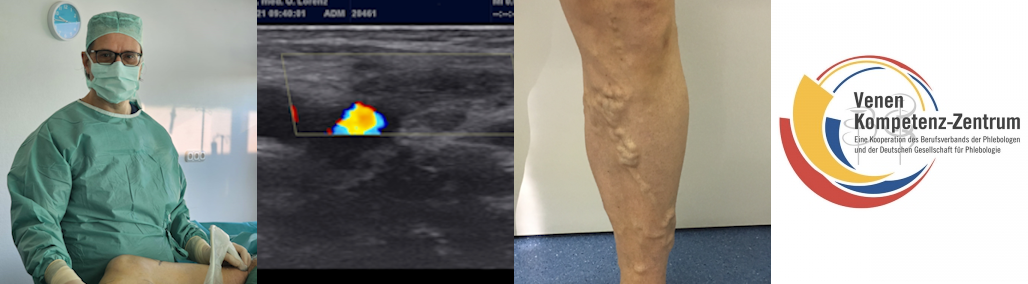

Über Venenbeschwerden klagen sehr viele Menschen. Krampfadern (Mittelhochdeutsch: „krumpe Ader“ =krumme Ader) sind dauerhafte, ausgeweitete, oberflächliche Venen gern mit Schlängelung oder Knäuelbildung, wobei die Erweiterung durch ein zu hohes Blutvolumen im Venensystem aufgrund einer ungenügenden Funktion der Venenklappen hervorgerufen wird.

- Seitenast-Varikose: Tritt an den kleineren Venenästen auf, die von den Stammvenen abzweigen. Diese sind oft deutlich als geschlängelte Erhebungen unter der Haut sichtbar.

Die individuelle Therapieempfehlung orientiert sich immer an der Art der Krampfadern, der Schwere der Funktionsstörung und eventuellen Begleiterkrankungen. Unsere Methoden umfassen das gesamte Spektrum an invasiven Behandlungen und vorzugsweise vertrauen wir insbesondere minimal-invasiven Hybridverfahren. Mit der Verödungsbehandlung oder Sklerotherapie kann zudem das ästhetisch störende Hauterscheinungsbild durch ugs. Besenreiser korrigiert werden.